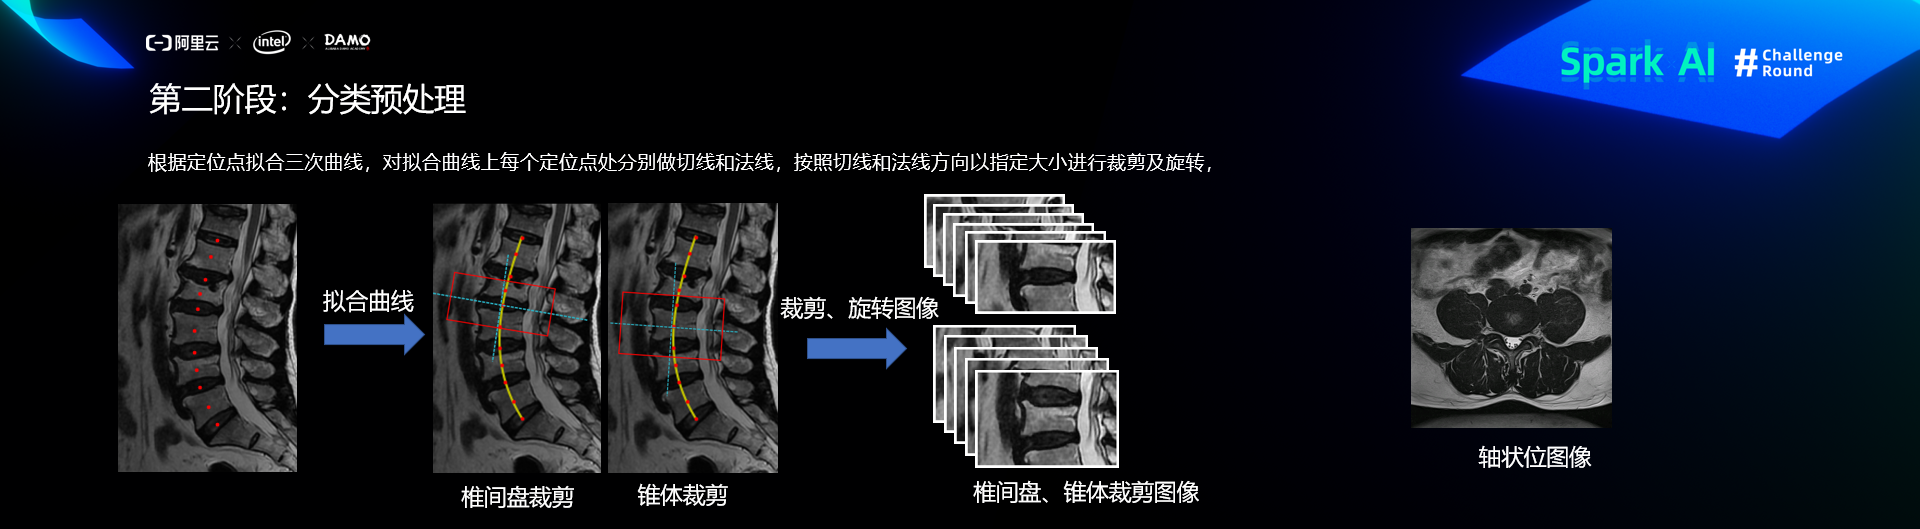

预处理